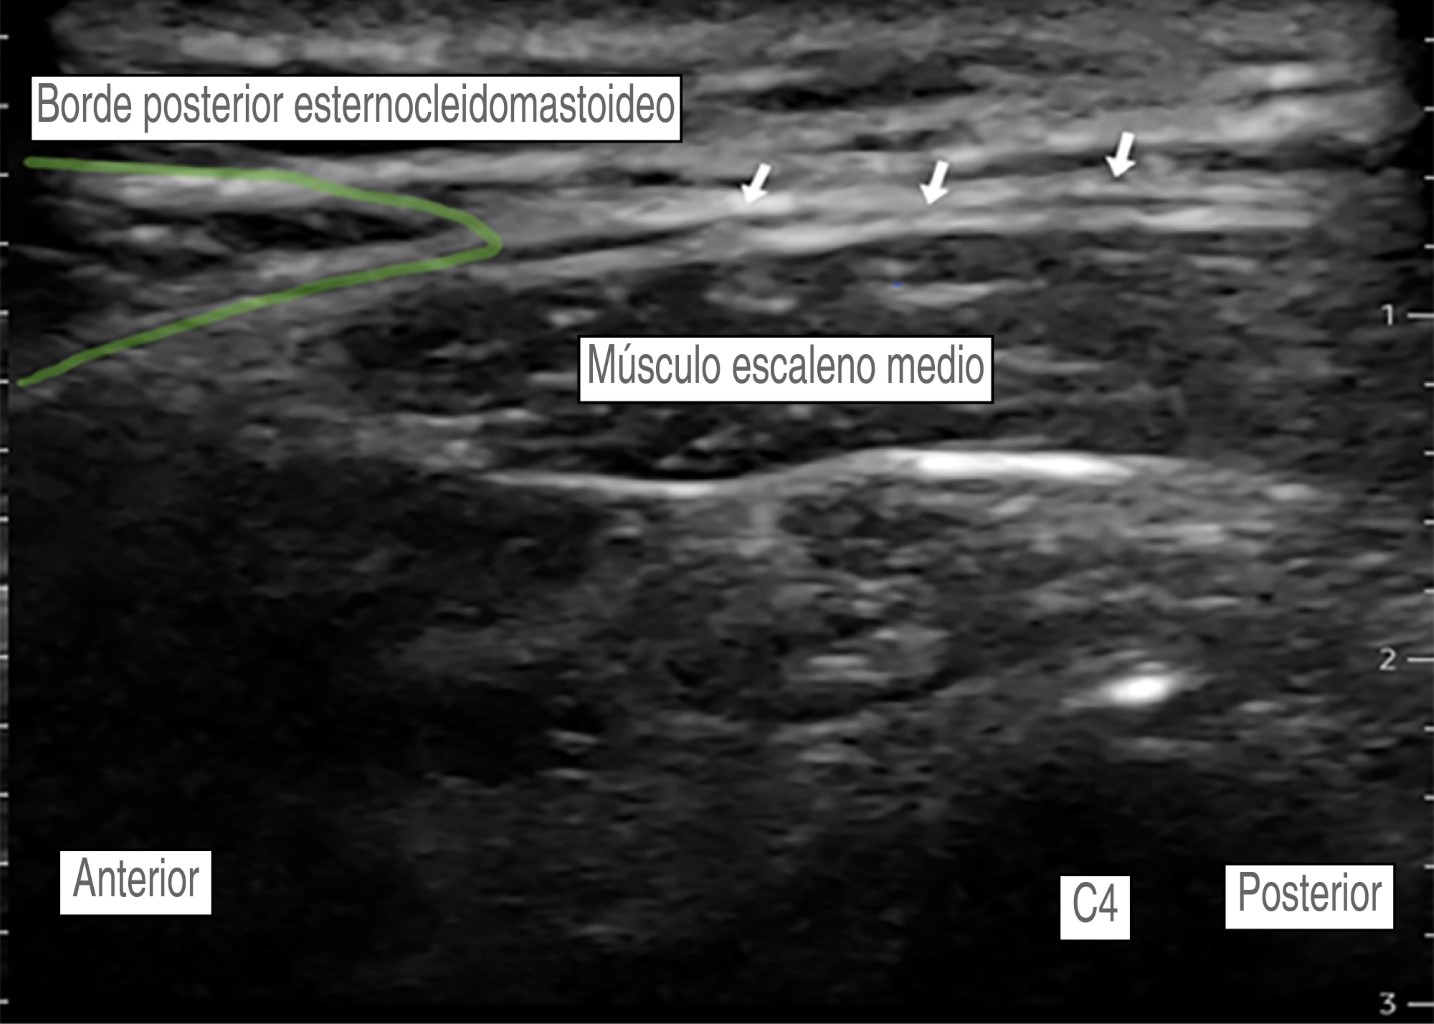

Hombre de 56 años, con diagnóstico de meningioma de la convexidad frontal, con un estado físico de la American Society of Anesthesiologists (ASA) II. Hipertensión arterial esencial en tratamiento regular con losartán 50 mg VO cada 24 horas, sin otros antecedentes. Peso: 87 kg, talla: 1.70 m. Presenta un cuadro clínico de tres meses de evolución caracterizado por cefalea holocraneana, trastornos del comportamiento (apatía, falta de motivación, indiferencia) sin datos de focalización neurológica. La imagen de resonancia magnética muestra una tumoración frontoparietal derecha de 8.2 × 5.1 cm que realza al contraste de forma homogénea, con efecto de masa significativo y desviación de la línea media de 13 mm. Ingresa a sala quirúrgica para craneotomía bifrontal y resección tumoral guiada por neuronavegación. En la sala quirúrgica bajo monitorización invasiva y anestesia total intravenosa con remifentanilo (0.15-0.2 μg/kg/min), propofol (90-120 μg/kg/min), lidocaína (1-2 mg/kg/h) y después de asegurar la vía aérea colocamos un bloqueo de escalpe guiado por USG. Se utilizó una sonda de USG lineal (10 MHz). Nervio supraorbitario y supratroclear: en situación transversal, colocamos la sonda en el hueso frontal sobre el reborde orbitario superior identificando el agujero supraorbitario (muesca). Con técnica en plano, la inyección es superficial al foramen (evitando la administración dentro del foramen), con un volumen de 1.5 mL de anestésico local, para asegurar una cobertura adecuada al nervio supratroclear colocamos otra inyección medial al supraorbitario de 1.5 mL de AL, visualizando su extensión bajo USG. No logramos identificar la arteria supraorbitaria (Figura 2). Nervio cigomático-temporal: colocamos el transductor en un plano coronal, sobre el límite anterior de la fosa temporal, posterior a la apófisis frontal del hueso cigomático, lo que nos deja visualizar tres estructuras: fascia temporal, músculo temporal y hueso temporal, colocamos dos inyecciones de 1.5 mL de AL, en dos puntos de referencia: el hueso temporal (profundo) y la fascia temporal superficial (Figura 3). Nervio auriculotemporal: en el mismo plano facial que el nervio anterior, colocando el transductor en sentido transversal entre el canto lateral del ojo y el trago, identificamos la arteria temporal superficial; el nervio corre en el mismo plano facial que la arteria y lo bloqueamos con 2 mL de AL, evitando la punción vascular (Figura 4). Nervio occipital mayor: colocamos la sonda de USG paralela a una línea que conecta el inión y la mastoides logrando identificar a la arteria occipital junto al nervio. Con inyección en plano utilizamos 2.0 mL de AL (Figura 5). Nervio auricular mayor y occipital menor: bloqueamos ambos nervios a través de un bloqueo de plexo cervical superficial, colocando la sonda transversal sobre la cara lateral del cuello, ubicando el borde posterior del músculo esternocleidomastoideo (ECM) en un punto medio entre la mastoides y la clavícula identificando el plexo como pequeños nódulos hipoecoicos profundos al borde posterior del ECM, el nervio auricular mayor se puede ver comúnmente sobre el músculo ECM. Con técnica en plano la inyección se realizó detrás del ECM, superficial a la fascia prevertebral con un volumen de 5 mL de AL (Figura 6). El bloqueo se realizó de forma bilateral utilizando 28 mL de bupivacaína isobárica a 0.5%, empleando un tiempo de 30 min, se evitó de forma efectiva la respuesta hemodinámica al pinchado, sin necesidad de aumentar la dosis de opioide, o requerir infiltración del área de colocación del pincho, se complementó la analgesia multimodal con paracetamol 1 g IV + ketoprofeno 100 mg IV, no se requirieron rescates de opioide en las 48 horas posteriores y hasta el egreso, se realizó una resección tumoral de 100% sin secuelas neurológicas, no se presentaron complicaciones asociadas al bloqueo de escalpe (punción vascular o déficit nervioso).

Figura 6